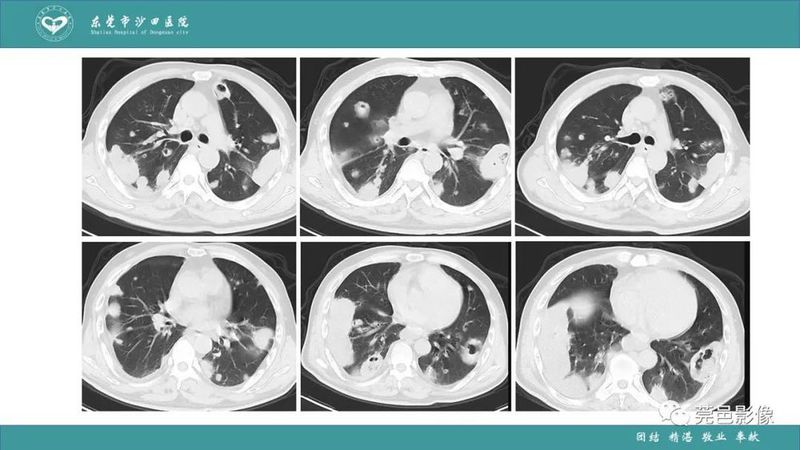

「肺炎克雷伯杆菌肺炎」影像学诊断+鉴别诊断